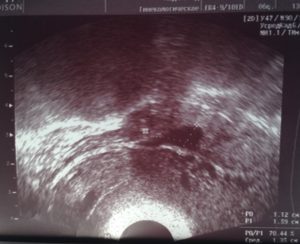

Если накапливается свободная жидкость в позадиматочном пространстве и прямокишечном углублении, это может быть вызвано острым воспалением органов малого таза. Название болезни – гнойный сальпингит. На УЗИ оно выглядит как расширение маточных труб (увеличение или удлинение) и наличие жидкости. Выявить данное заболевание можно по таким признакам:

При сдаче анализов диагноз подтвердят большое количество лейкоцитов, СОЭ и обнаружение гноя при пункции заднего свода. Лечение подразумевает операционное вмешательство.

При этом обязательно удаляется лишняя жидкость, купируется острое проявление воспаления, подавление воздействия микробов, обрабатывается очаг поражения и корректируется метаболическое нарушение.

- гнойный сальпингит. При разрыве пиосальпинкса гной попадает в брюшную полость и в «карман», расположенный с задней стороны матки. У пациентки развиваются дополнительные симптомы — повышается температура, болит живот. В крови увеличиваются лейкоциты. Требуется срочное хирургическое вмешательство. Будет удалена лишняя жидкость, а затем женщине предстоит длительное лечение, купирующее воспаление, и антимикробная терапия;